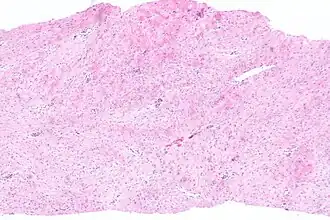

![]() Imagen histológica en bajo aumento de un tumor desmoides. Tinción hematoxilina-eosina. | ||

El patrón histológico característico consiste en fibroblastos con características citológicas benignas organizados en fascículos anchos unidos entre colágeno denso.[4]